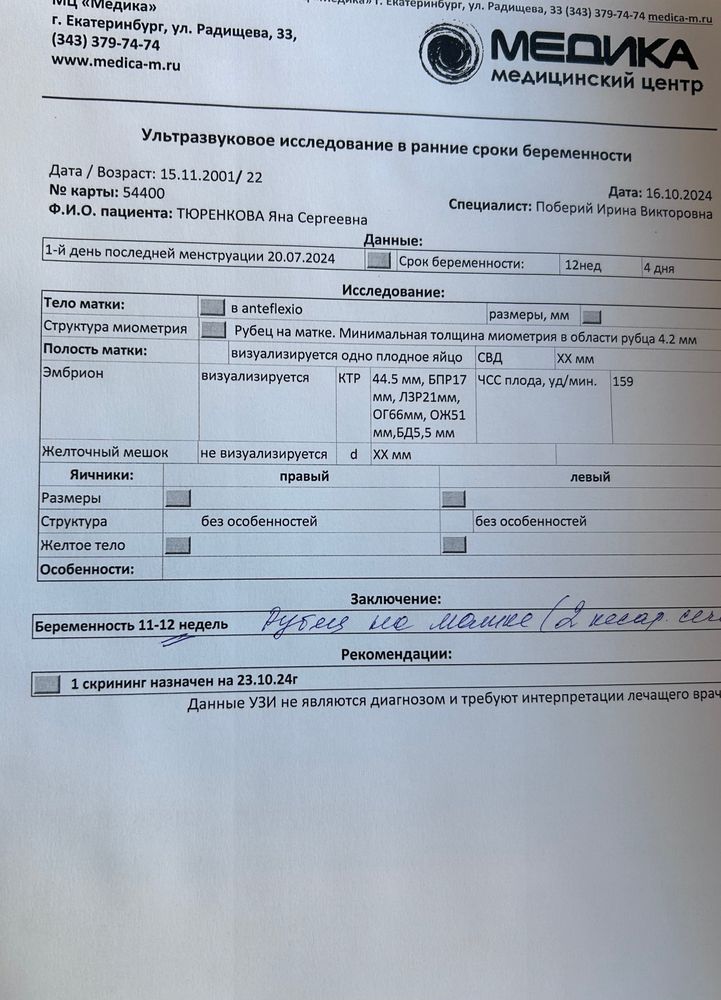

Всем привет девочки, сходила внепланово на узи перед скринингом для своего спокойствия, все посмотрели, что смогли замерили, смущает что ктр она сказала 44,5-45 это по таблице 11,3, а у меня по узи прошлому было 11,5, при этом все части тела на 12 недель, но самое главное никаких пороков она пока что не увидела, 23 числа уже прям на профессиональный скрининг поеду с кровью, надеюсь и там все хорошо, кстати предположили мальчика, но говорит не точно, потом проверим)